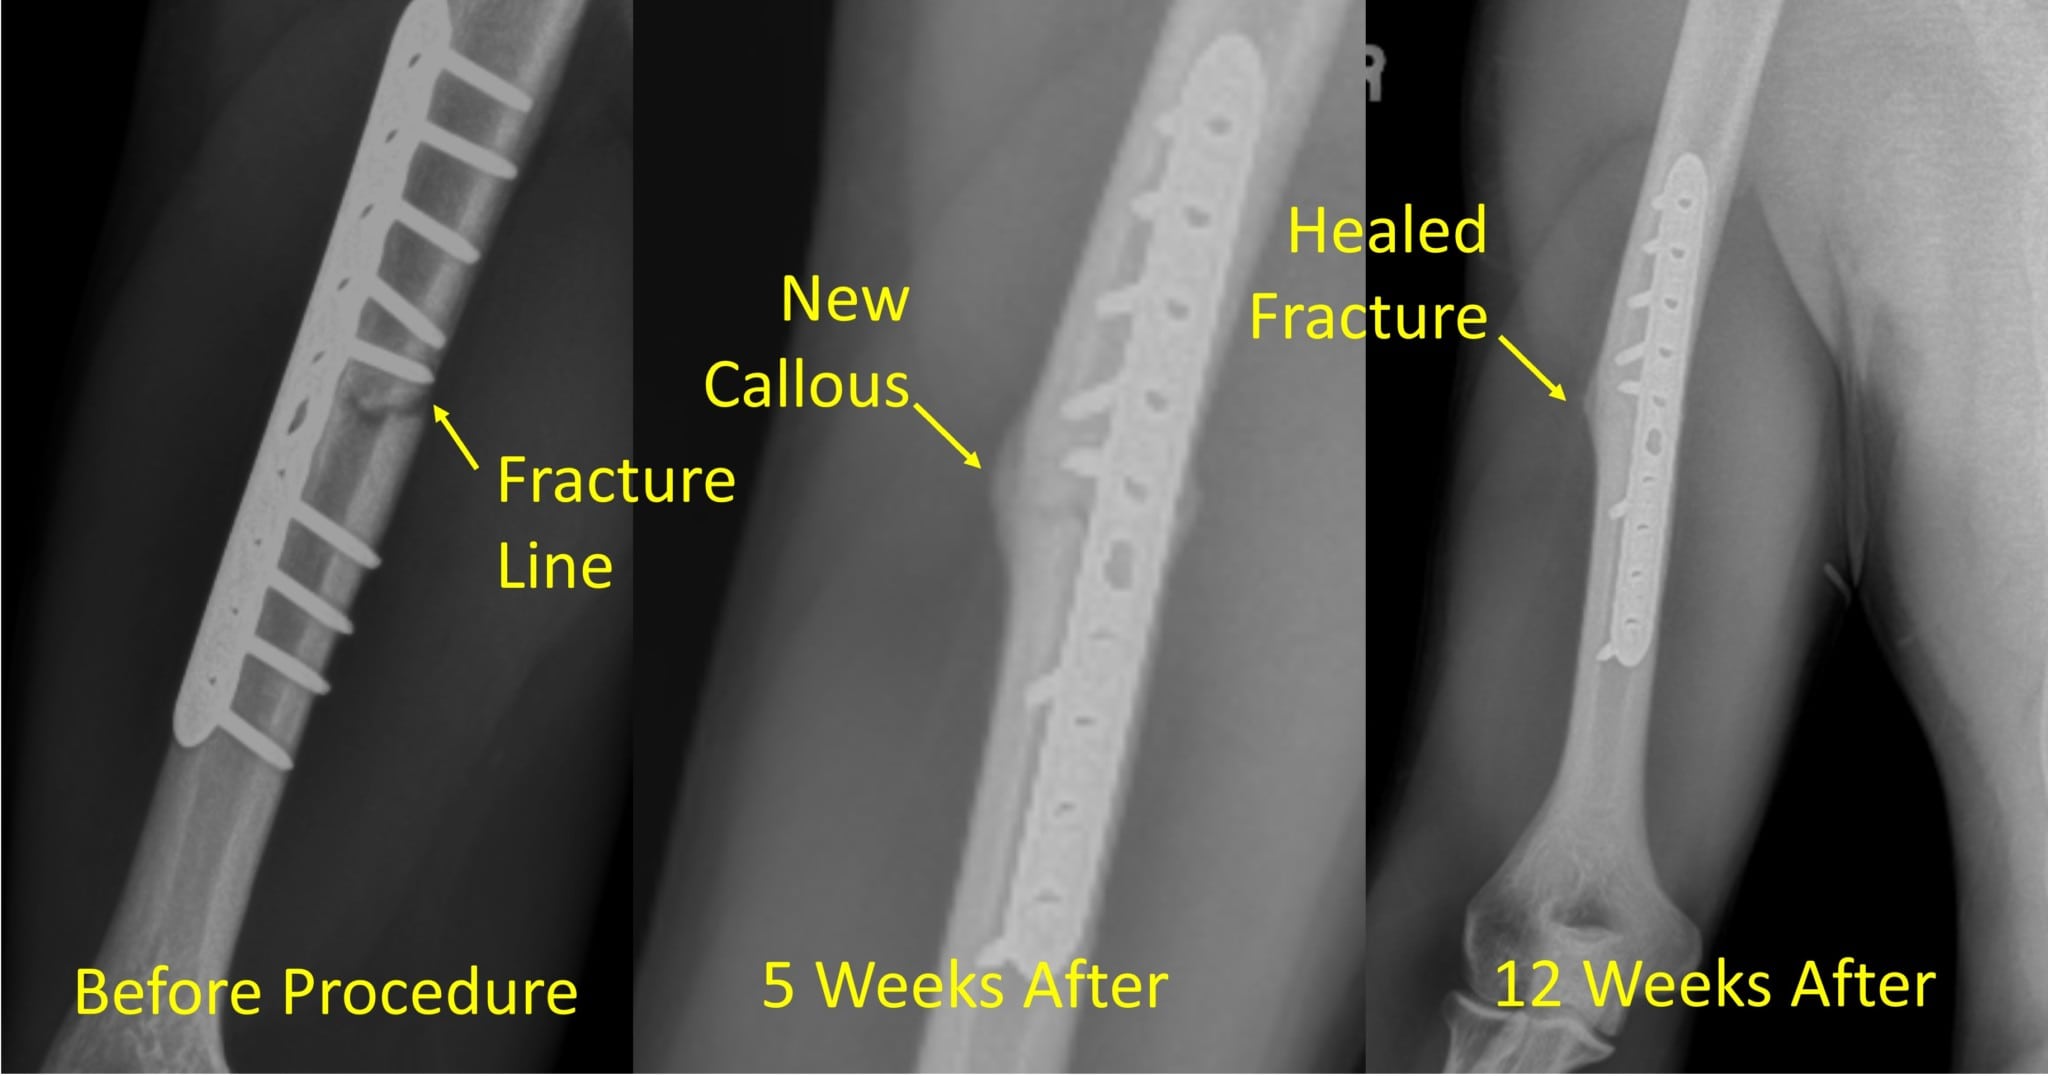

Cureus Fracture Nonunions and Delayed Unions Treated With Low Non Union Fracture X Ray fracture patterns in higher energy injuries (i.e.: nonunions occur when the bone lacks adequate stability, blood flow/nutrition, or both. — this case shows abnormal fracture healing in the tibia and fibula with pseudoarticulation formed in the tibial. Comminution, bone loss, or segmental patterns) have a higher degree of soft. They also are more likely if the bone. Non Union Fracture X Ray.

Cureus Fracture Nonunions and Delayed Unions Treated With Low Non Union Fracture X Ray nonunions occur when the bone lacks adequate stability, blood flow/nutrition, or both. — this is the most common 'natural' healing process, whereby the fracture ends are placed close to each other (but not apposed), with. fracture patterns in higher energy injuries (i.e.: Comminution, bone loss, or segmental patterns) have a higher degree of soft. — this. Non Union Fracture X Ray.